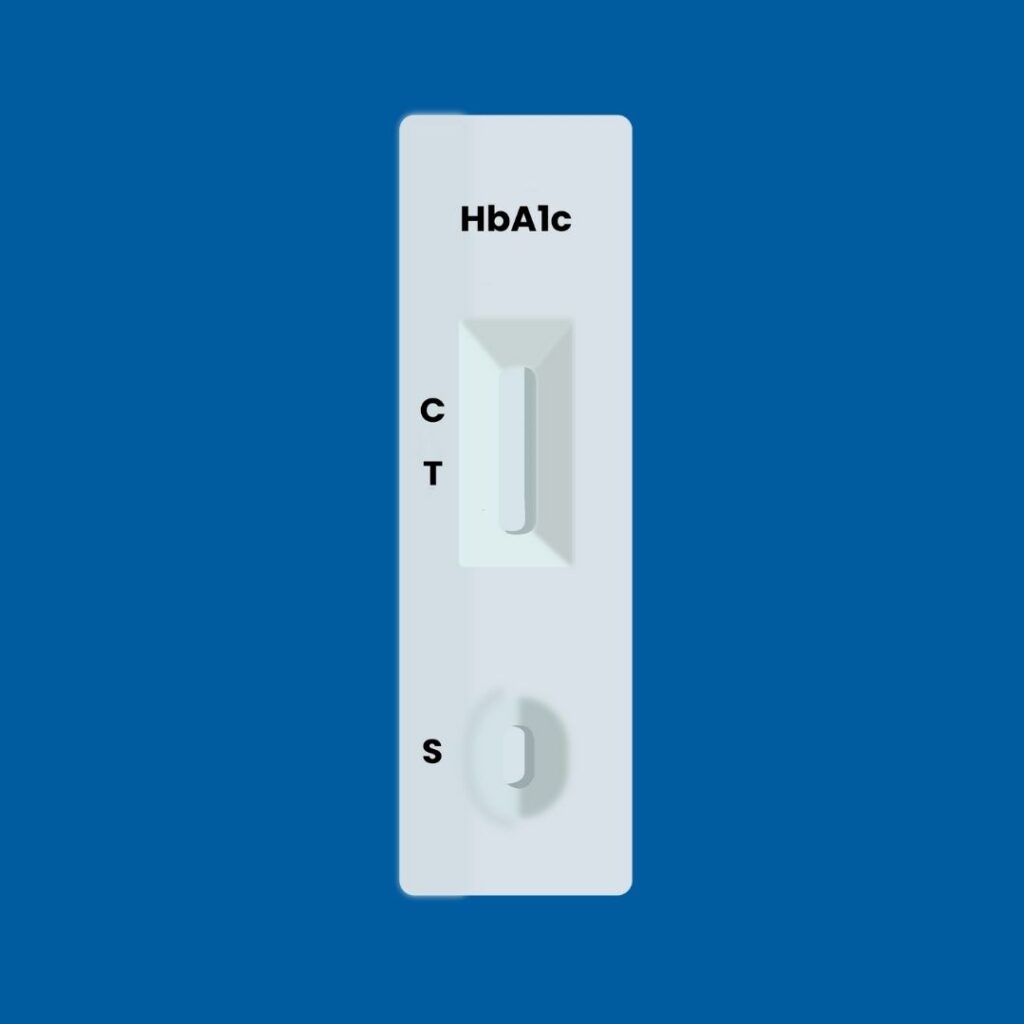

Aquí es donde Hemoglinet redefine el panorama del diagnóstico y control de la diabetes. Esta innovadora prueba de hemoglobina glicosilada (HbA1c) elimina la necesidad de equipos sofisticados y costosos.

Con solo unas gotas de sangre, Hemoglinet permite una detección cuantitativa in situ, lo que significa que el análisis puede realizarse en cualquier lugar, desde un consultorio médico hasta un entorno rural, sin la infraestructura de un laboratorio tradicional.

Si la prueba de Hemoglinet muestra dos líneas encendidas, indica que el nivel de hemoglobina glicosilada del paciente está por encima del 6.5%, un claro signo de descontrol o diagnóstico de diabetes que requiere atención inmediata.